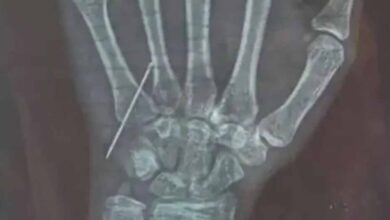

0

गोरखपुर में डॉक्टर की लापरवाही: 15 साल की बच्ची की नस में तोड़ा नीडल, CMO ने जांच के आदेश दिए